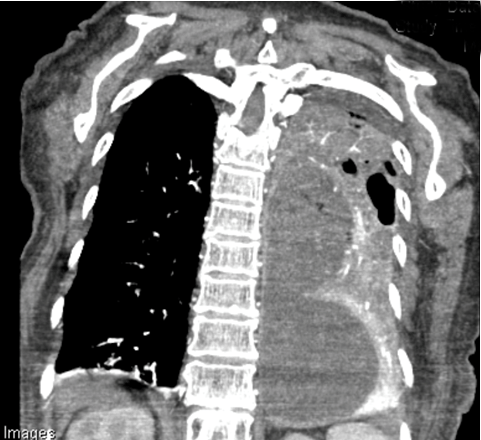

A 77-year-old female, with a 30-pack year smoking history and current 1/2 pack per day smoker, presented to the emergency department with progressive shortness of breath and hemoptysis. The patient had seen her primary care provider one week prior to arrival and was advised to have a computed tomography scan of the chest, which showed 8x4.6x10.4 cm cystic/necrotic septated mass in the left posterior mediastinum. There was also mass effect of adjacent structures including the left lower pulmonary vein which demonstrated a thrombus within the lumen (Figure 1) (Figure 2). She was started on apixaban for this questionable tumor extension versus bland clot. Hemoptysis had become significantly heavier since starting Eliquis, so she came to the emergency department for further evaluation.

Figure 2: Computed tomography scan of chest coronal view showing 14x9x6 cm large mass.